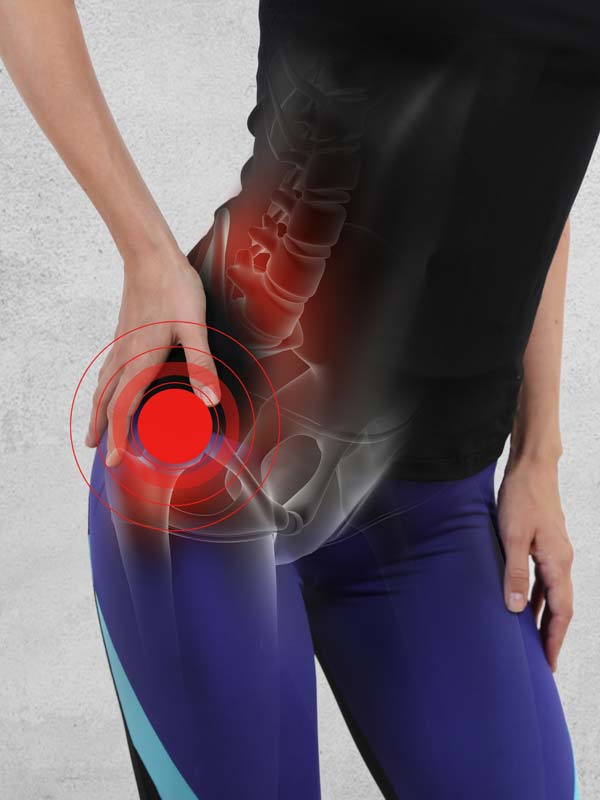

An educational resource on biologic reconstruction and arthroscopic techniques to restore hip function and prevent arthritis in children and young adults.

Although total hip replacement is very successful in pain relief, it cannot come close to the native hip function in active people. Hip arthroscopy and open surgical dislocation have provided opportunities for better understanding of hip disorders and for the development of biologic reconstruction options.

Hip impingement and dysplasia are now recognized as common causes of hip arthritis. Early results of surgical correction have been shown to prevent arthritis. Femoral head contour can be restored and maintained with medical management in the early stages of avascular necrosis.